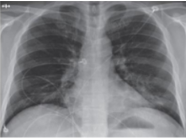

Hình ảnh ở bên là hình chụp phổi của một bệnh nhân nhiễm vi rút Covid-19. Thiết bị để chụp hình ảnh ở trên đã sử dụng tia nào sau đây?

Đáp án đúng là: B